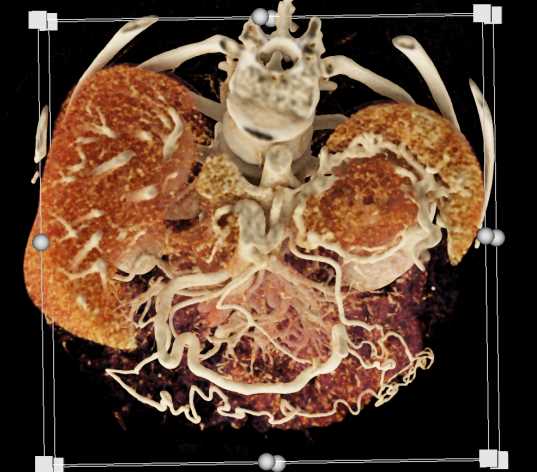

Neuroendocrine Tumor Pancreas